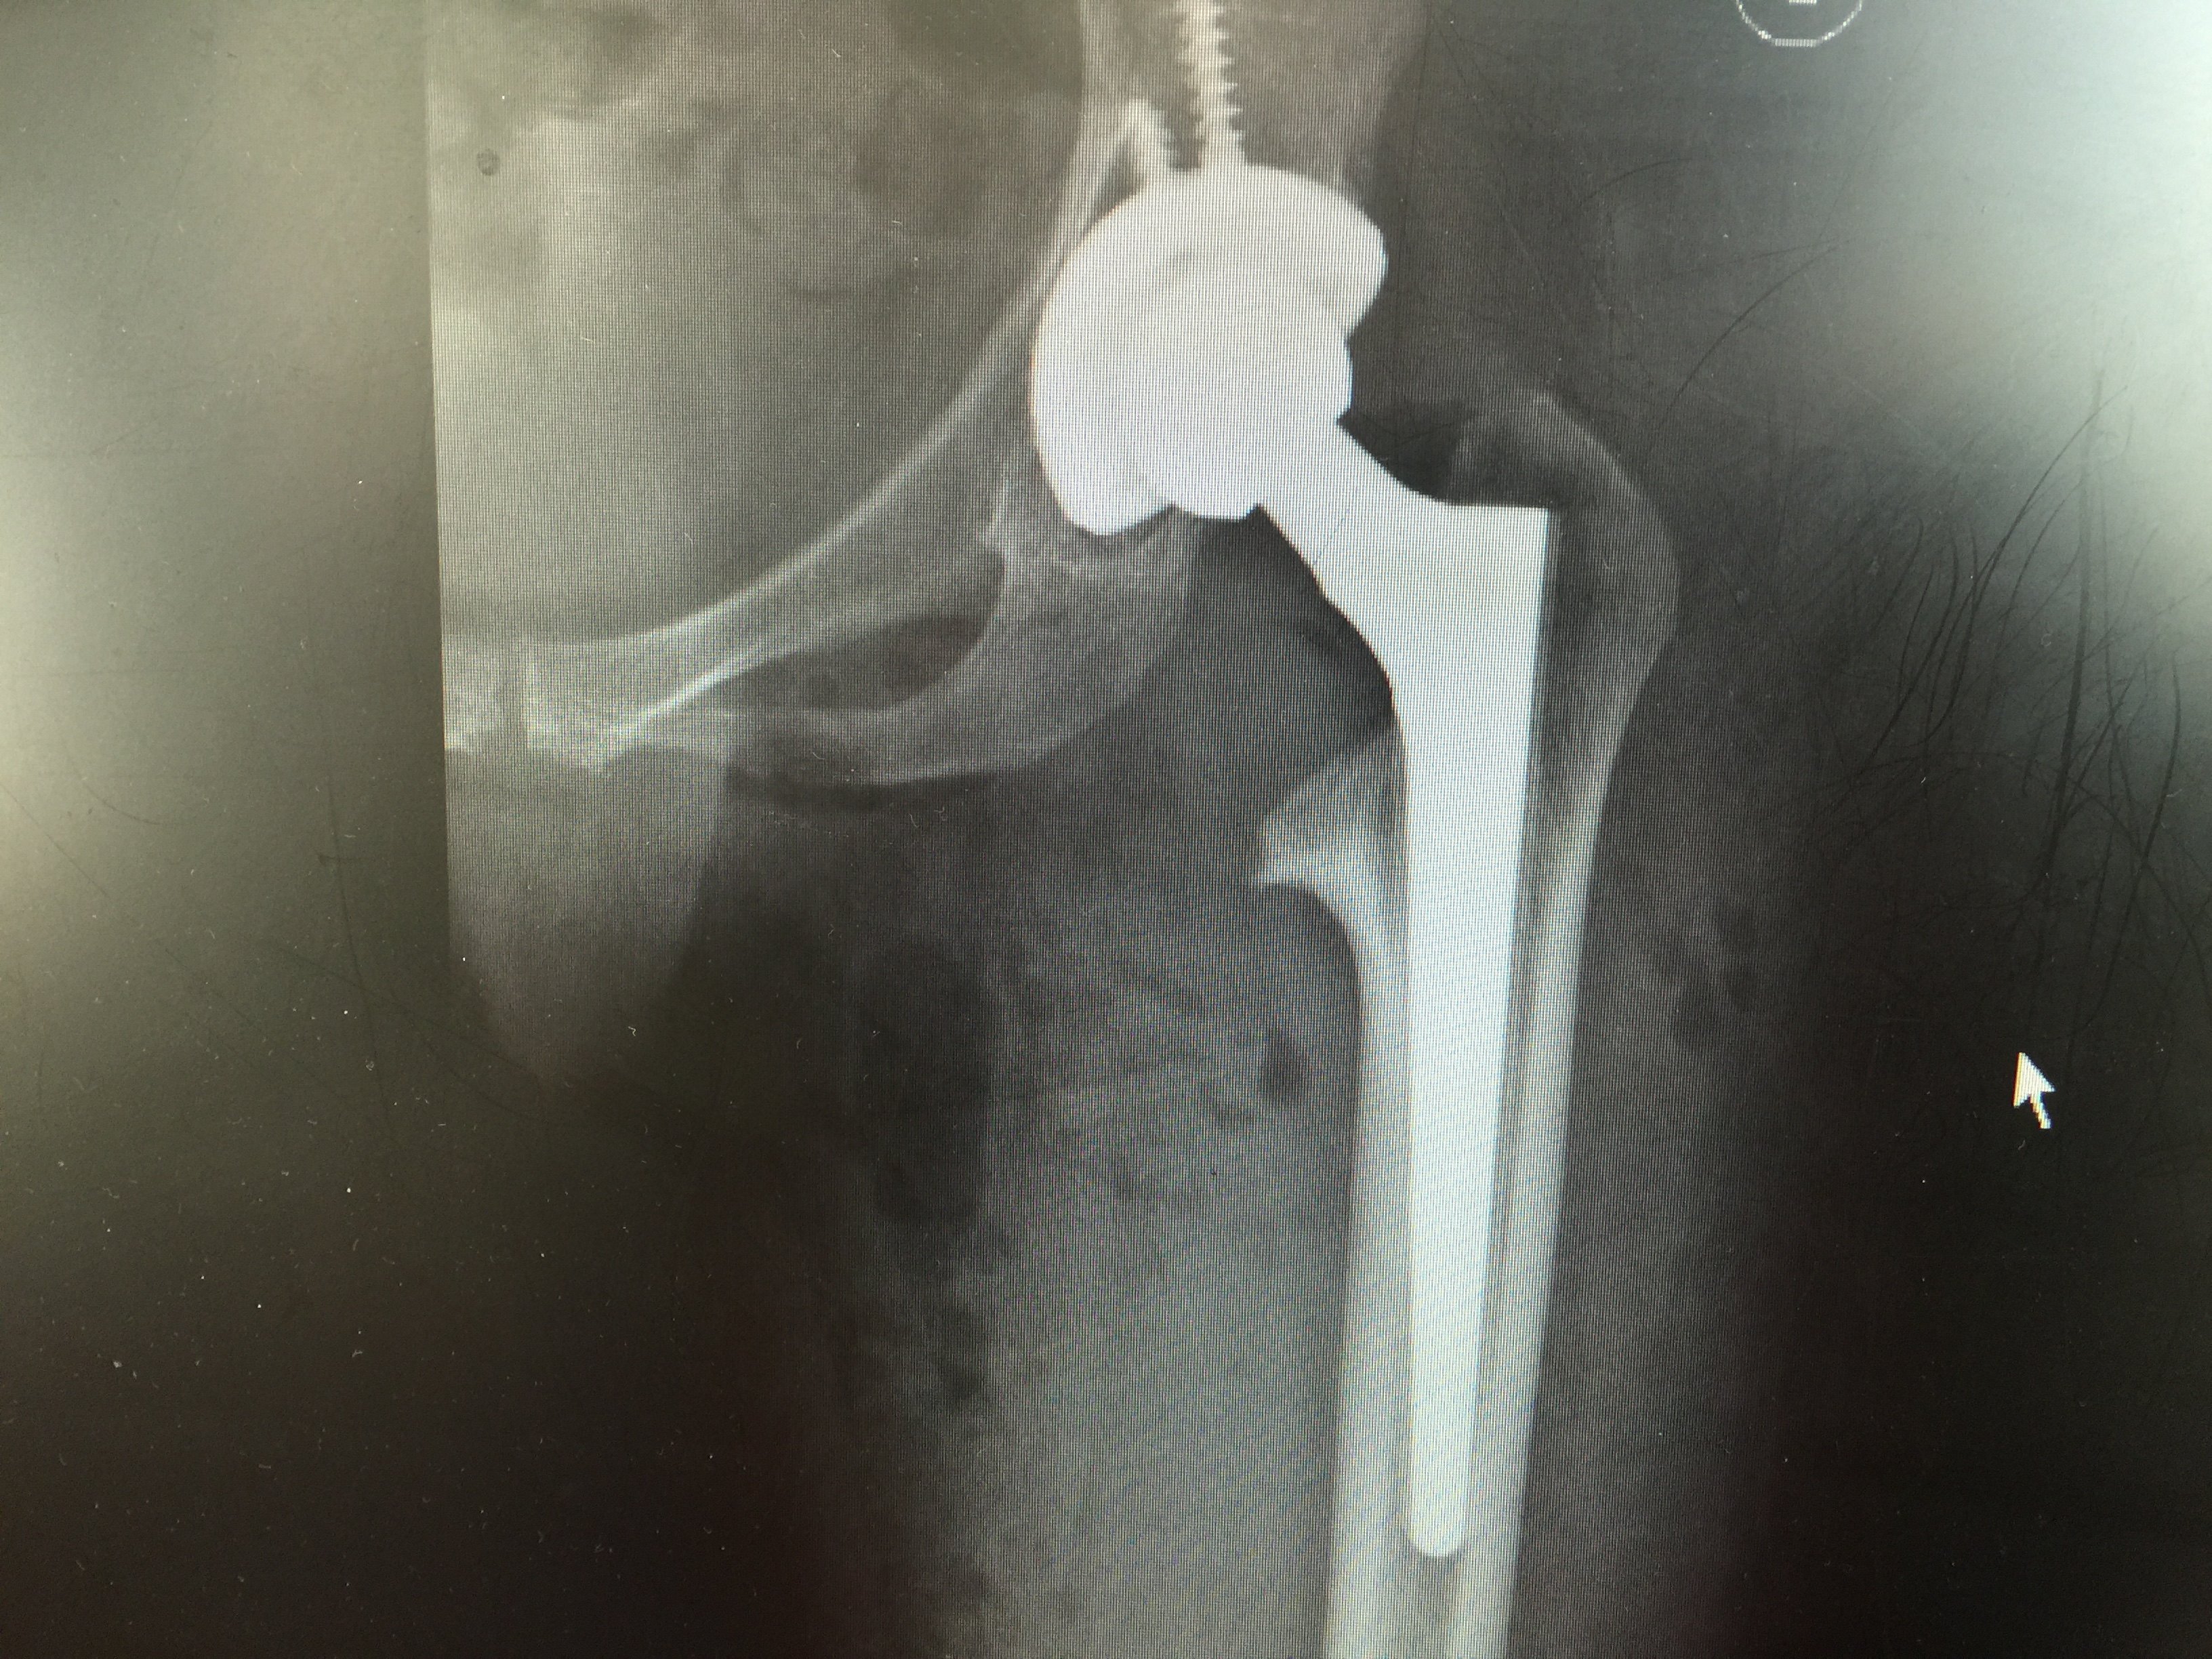

先天性扁平髋髋关节置换